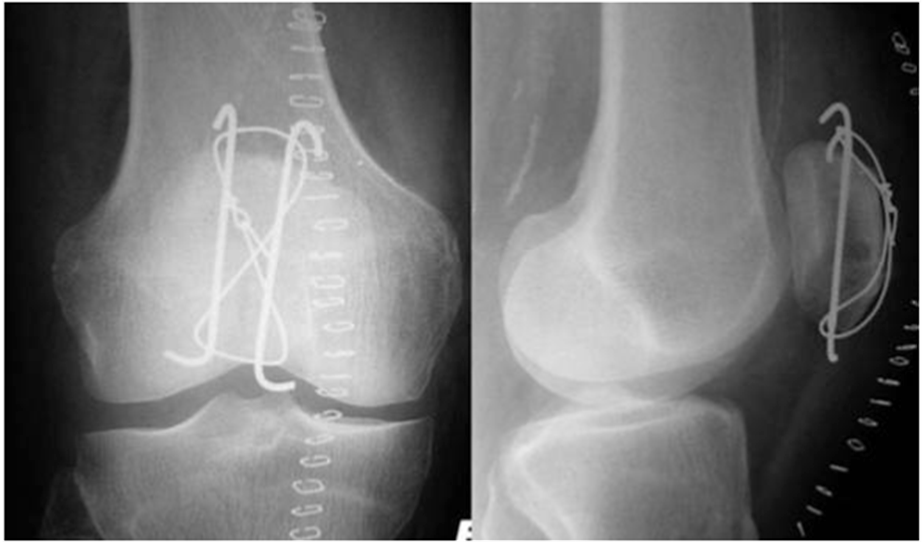

Лечение перелома надколенника зависит от смещения отломков. При переломе без смещения возможно лечение гипсовой повязкой, при малейшем смещении — необходима операция на коленной чашечке. Смещение отломков составной поверхности надколенника должно быть обязательно устранено на операции, поскольку именно суставная поверхность надколенника скользит по мыщелкам бедренной кости при разгибании ноги в коленном суставе. При наличии смещения либо будет вообще отсутствовать разгибание, либо будет формироваться артроз бедренно-надколенникового сочленения. Отломки при переломе надколенника можно фиксировать винтами, спицами, проволокой.

Фиксация перелома надколенника винтами.

Наиболее распространённый способ фиксации – это остеосинтез по Веберу, хирургу, который придумал эту операцию. При этой операции для фиксации используются спицы и проволока (продемонстрировано на схеме ниже).

Рентгенограммы после остеосинтеза надколенника по Веберу.

Как фиксируют надколенник? Вариант остеосинтеза определяется типом перелома. При поперечном переломе сопоставить и скрепить отломки можно с посощью специальной медицинской проволоки (серкляжа) и спиц. Такую операцию называют именем ее изобретателя – Вебера.

Иногда отломки успешно скрепляются винтами, или винтами и проволокой.